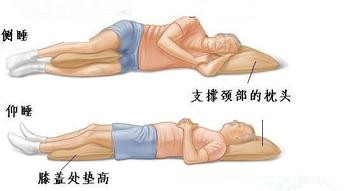

强直性脊柱炎患者的正确睡眠姿态

人的一生中睡眠时间占据了三分之一,睡眠是人体的一个自我调理的 ...